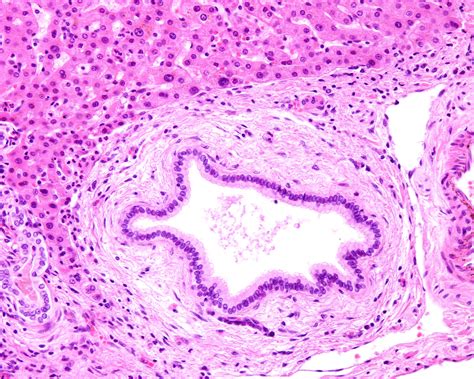

• Intrahepatic bile duct cancer: Located within the liver.

• Perihilar (Klatskin) bile duct cancer: Located where the bile ducts exit the liver.

• Distal bile duct cancer: Located closer to the small intestine.